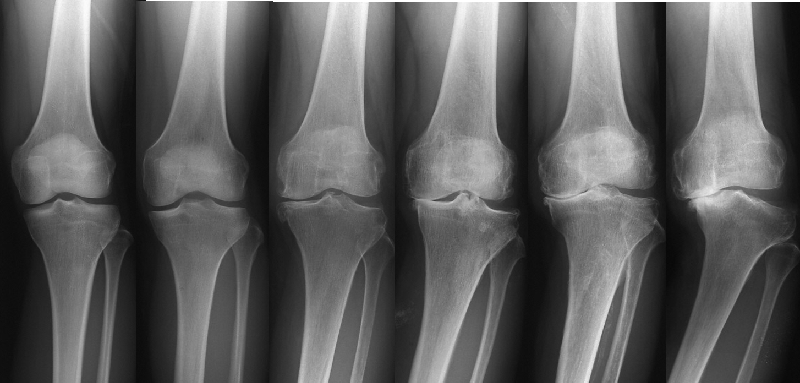

左が正常なひざ関節、右に行くほど変形が大きくなっています。